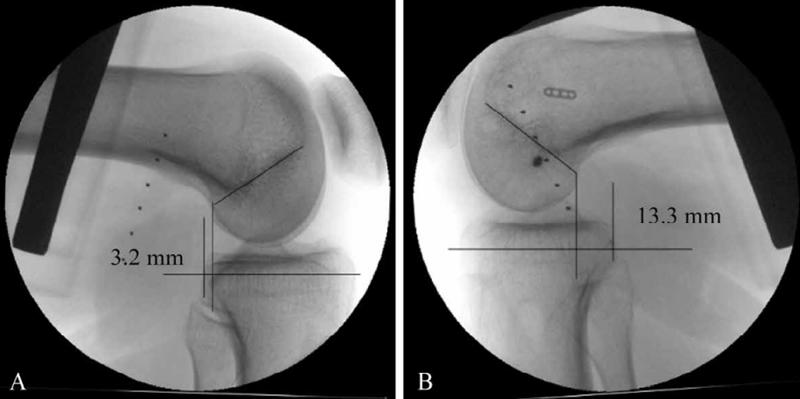

后方应力位或跪位X线检查是诊断PCL损伤的可靠方法(图6),对比健侧,后移增加0~7mm为PCL部分损伤(图7),8~11mm为单纯PCL全部断裂(图8),12mm以上可能为PCL和PLC等其他结构合并损伤(图9)。

图8 PCL完全断裂X线影像

应力位X线片示患侧(B)胫骨后移超过健侧(A)10.1mm

图9 PCL完全断裂合并PLC损伤X线影像

应力位X线片示患侧(B)胫骨后移超过健侧(A)13.5mm